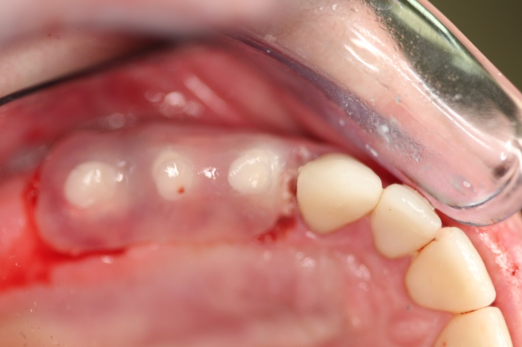

Fig 6. After splint removal (12 weeks postoperatively).

Figure 6

Figure 3 through Figure 5 show the fitting of a one-piece multiple splint using a light-cured acrylic, along with flowable composite to adhere the splint to the three ceramic dental implants. The splint was to remain out of occlusion, without any occlusal forces for the 12-week osseointegration period. The patient was instructed to chew on the other side of her mouth for the 12 weeks before returning to the dental practice for simple removal of the splint. Removal of the splint revealed optimum results. The soft tissues were pink, with keratinized gingival margins completely surrounding the ceramic implants and consistent with what most dentists observe with the periodontium around periodontally healthy natural teeth (Figure 6 and Figure 7).